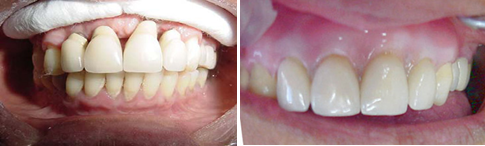

Caso de epítese (gengiva artificial de porcelana).

Situação que o paciente se apresentou no consultório para colocação de implantes e restabelecimento da estética e função dos dentes. Como o tecido ósseo havia sido reabsorvido, para a realização dos implantes, enxerto de ósseo e plasma rico em plaquetas (PRP) teve que ser realizado. Na fotografia vemos os parafusos, fixando os blocos de osso que colocados, e recobertos com PRP (Fotos).

Nestas fotografias estão: O PRP utilizado junto com o enxerto de osso e os implantes colocados 6 meses após a cirurgia.

A primeira fotografia mostra o caso após a colocação das coroas provisórias sem a gengiva artificial de resina (epítese). Na segunda fotografia o caso concluído e a gengiva artificial colocada, mostrando a recuperação ideal possível da estética do paciente. Importante salientar a satisfação e importância desses procedimentos para o paciente, que havia se submetido a esse longo tratamento.